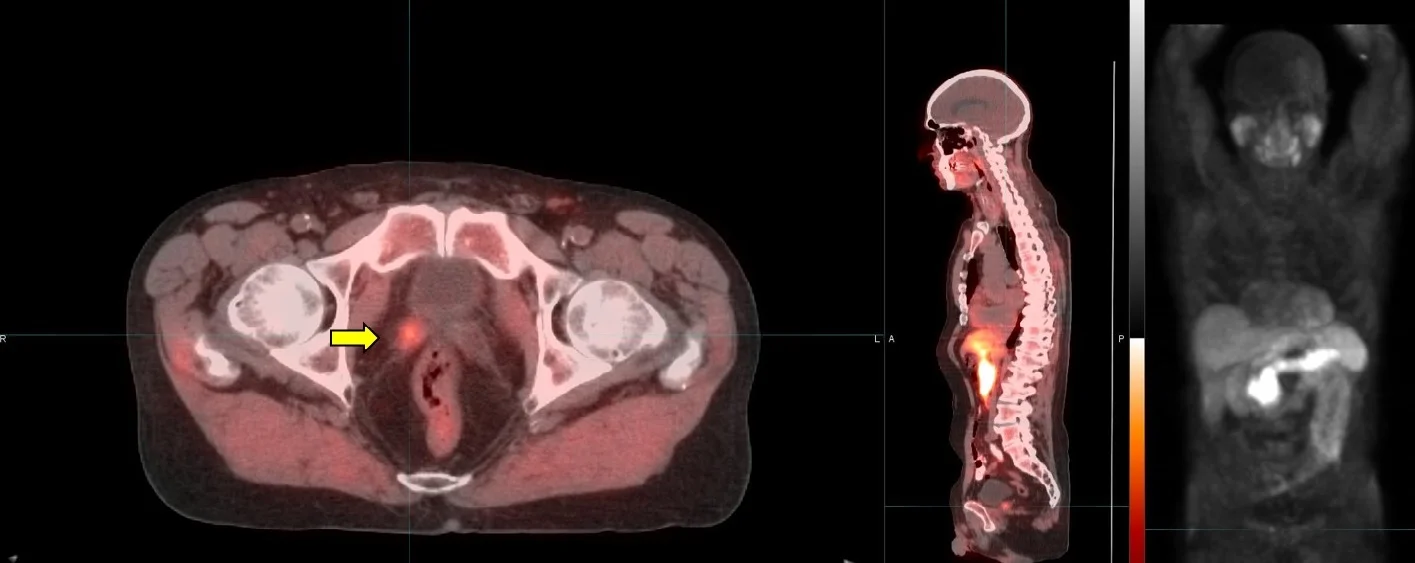

Today, cancer patients have more treatment options than ever before. The main purpose of imaging in oncology is early detection to enable interception if not prevention of full-blown disease, such as the appearance of metastases. Because biochemical changes occur well in advance of changes in anatomy, PET/CT molecular imaging provides especially early localization of disease. With this information, more optimal treatment selections can be made.

Positron Emission Tomography (PET/CT) is a major diagnostic imaging modality used predominantly in determining the presence and severity of cancers. It is currently the most effective way to check for cancer recurrence and to assess the response to treatment. Studies demonstrate that PET/CT offers significant advantages over other forms of imaging such as CT or MRI scans in diagnosing disease. Several hundred thousand clinical PET/CT patient studies are performed annually around the country.

PET/CT images demonstrate the chemistry of organs and other tissues such as tumors. A radiopharmaceutical, such as FDG (fluorodeoxyglucose), which includes both sugar (glucose) and a radionuclide (a radioactive element) that gives off signals, is injected into the patient and its emissions are measured by a PET/CT scanner.